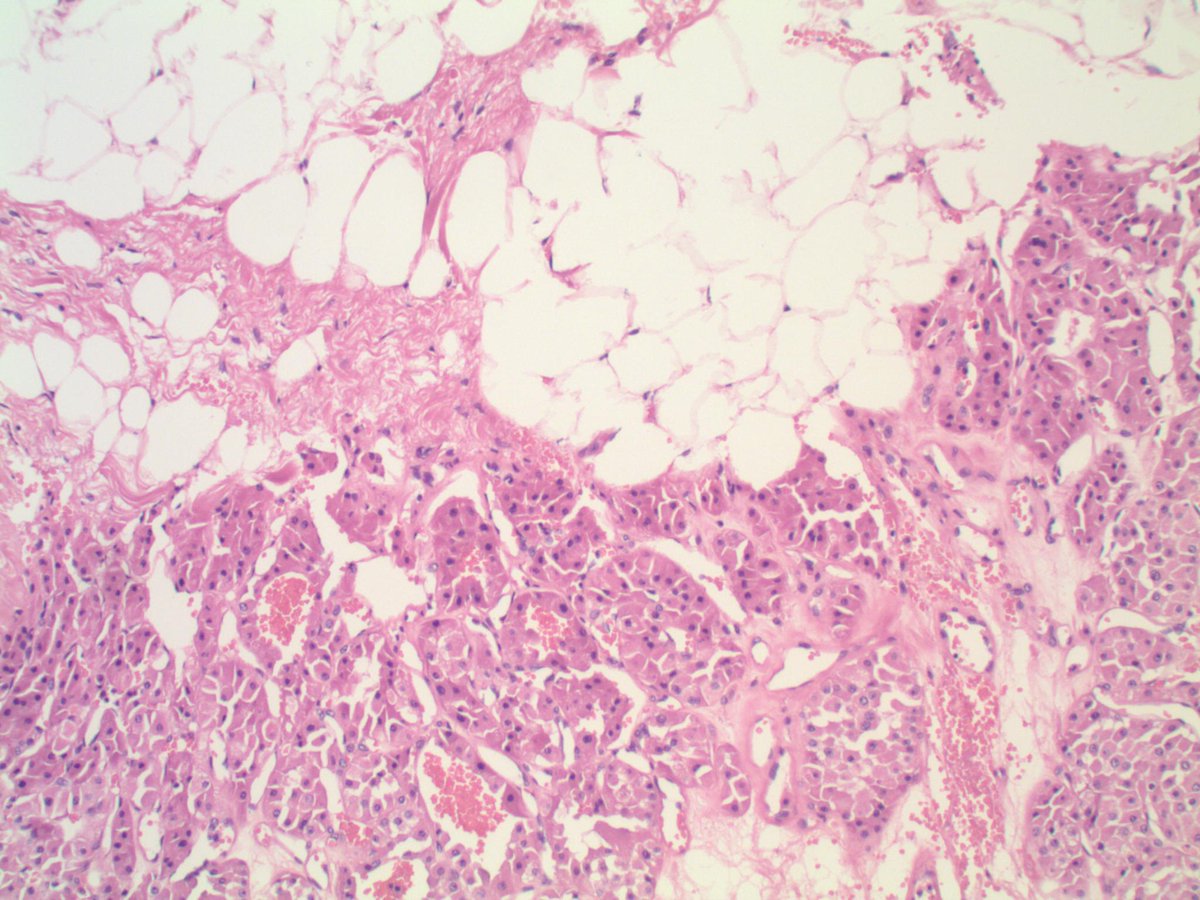

#GUpath nephrectomy: renal oncocytoma, "invading" perinephric adipose tissue ✔️does not necessarily itself portend malignancy PMID: 9255250 PMID: 21166703